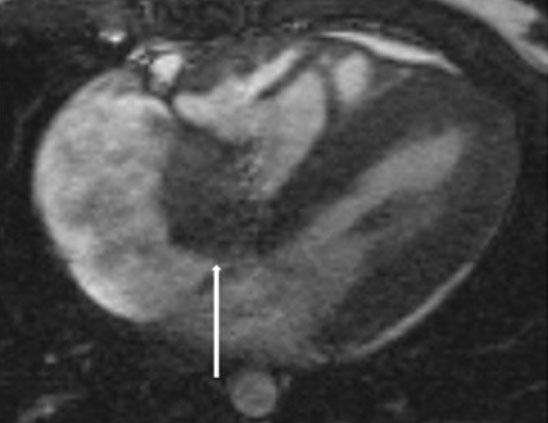

A transthoracic echocardiogram performed showed a large mobile heterogenous echogenic mass attached to the anterior leaflet of the tricuspid valve, without obstruction to inflow. During systole, the mass prolapsed through the valve causing leaflet distortion and mild-to-moderate eccentric tricuspid regurgitation (Figure 1). The heart structure and function were otherwise normal. Cardiac magnetic resonance imaging (CMR) was performed for diagnostic tissue characterization. On steady state free precession (SSFP) sequences, the mass appeared as isointense, well circumscribed, mobile valve nodules with turbulent flow. Tissue characterization revealed a T1 hypointense and T2 isointense soft tissue mass without early perfusion or late gadolinium enhancement (Figure 2). Imaging findings were consistent with a benign tumor with the differential diagnosis of an infectious or inflammatory mass, myxoma, papillary fibroelastoma, or teratoma [1].

Figure 1: Subcostal color compares transthoracic echocardiogram imaging showing a nodular appearing mass (white arrow) attached to the tricuspid valve leaflet. The mass prolapses in systole into the right atrium resulting and results in moderate tricuspid regurgitation (yellow arrow).